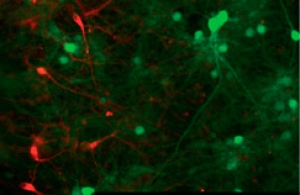

Dopo aver testato l’attività dei neuroni, Weick e colleghi li hanno trapiantati nel cervello di alcuni topi vivi, inserendoli nell’ippocampo, un’area coinvolta nell’elaborazione dei ricordi e nell’orientamento, le cui cellule sono facilmente identificabili. Infine, dopo aver prelevato delle porzioni di questo tessuto, ne hanno controllato l’attività. Lo stesso metodo utilizzato in precedenza ha permesso loro di osservare il comportamento dei neuroni in vivo e di scoprire che le cellule trapiantate non solo erano perfettamente integrate nel circuito cerebrale dei topi, ma potevano anche comunicare con questo, inviando stimoli inibitori o eccitatori.

Credit per l’immagine: National Academy of Science